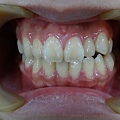

患者年約19歲,女性,於門診中表示想做矯正治療改善外觀, 因為看起來暴暴的,她不喜歡;經醫師檢查後發現患者的牙弓 太小,加上有4顆智齒爭扎欲出,但卻沒有空間,所以導致牙 齒往前暴的現象。